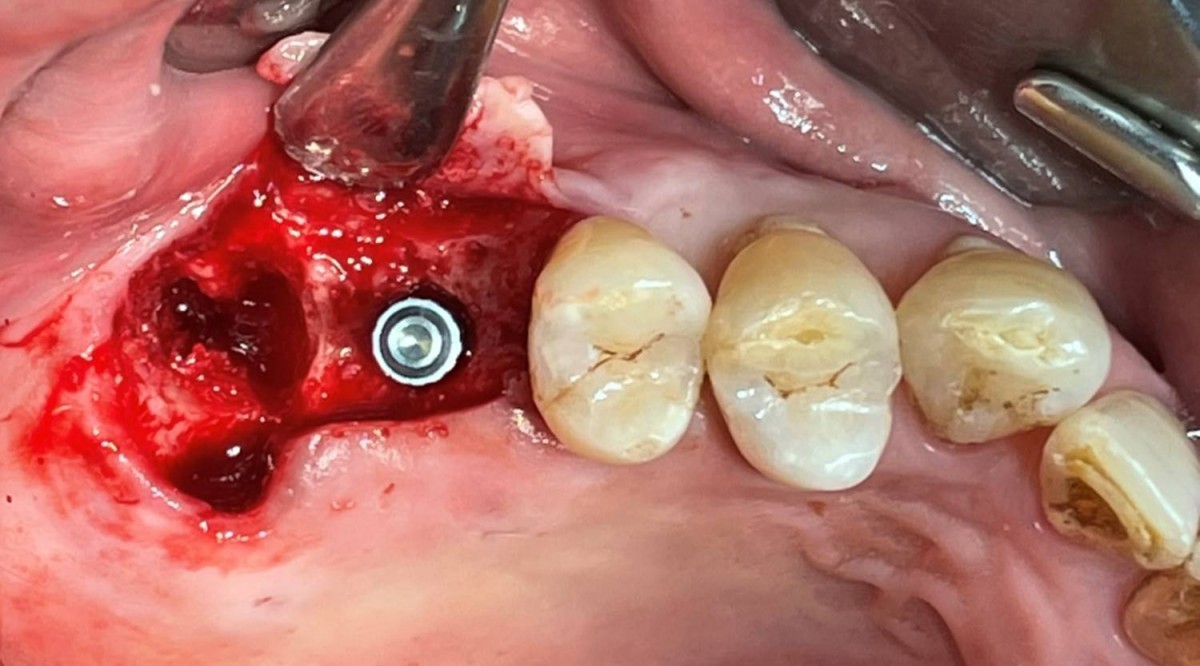

Maxillary Sinus Graft, 2 Implants, Crown Contouring

<GCaks> A 56-year-old male patient had pain-inducing caries, and perio-involved tooth mobility resulted in a tooth fracture at 1st molar. And it was removed months ago. He was a heavy smoker and showed poor oral hygiene.